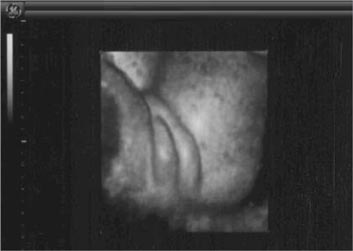

Blutflußmuster (Nabelschnurarterie)

Mit einer Farbdoppleruntersuchung (Blutflußmessung) der mütterlichen Blutgefäße in der 22. SSW kann überprüft werden ob eine erhöhte Wahrscheinlichkeit besteht, eine Schwangerschaftserkrankung (Gestose) zu entwickeln und ob bei dem  Kind eine Wachstumsverzögerung zu erwarten ist.